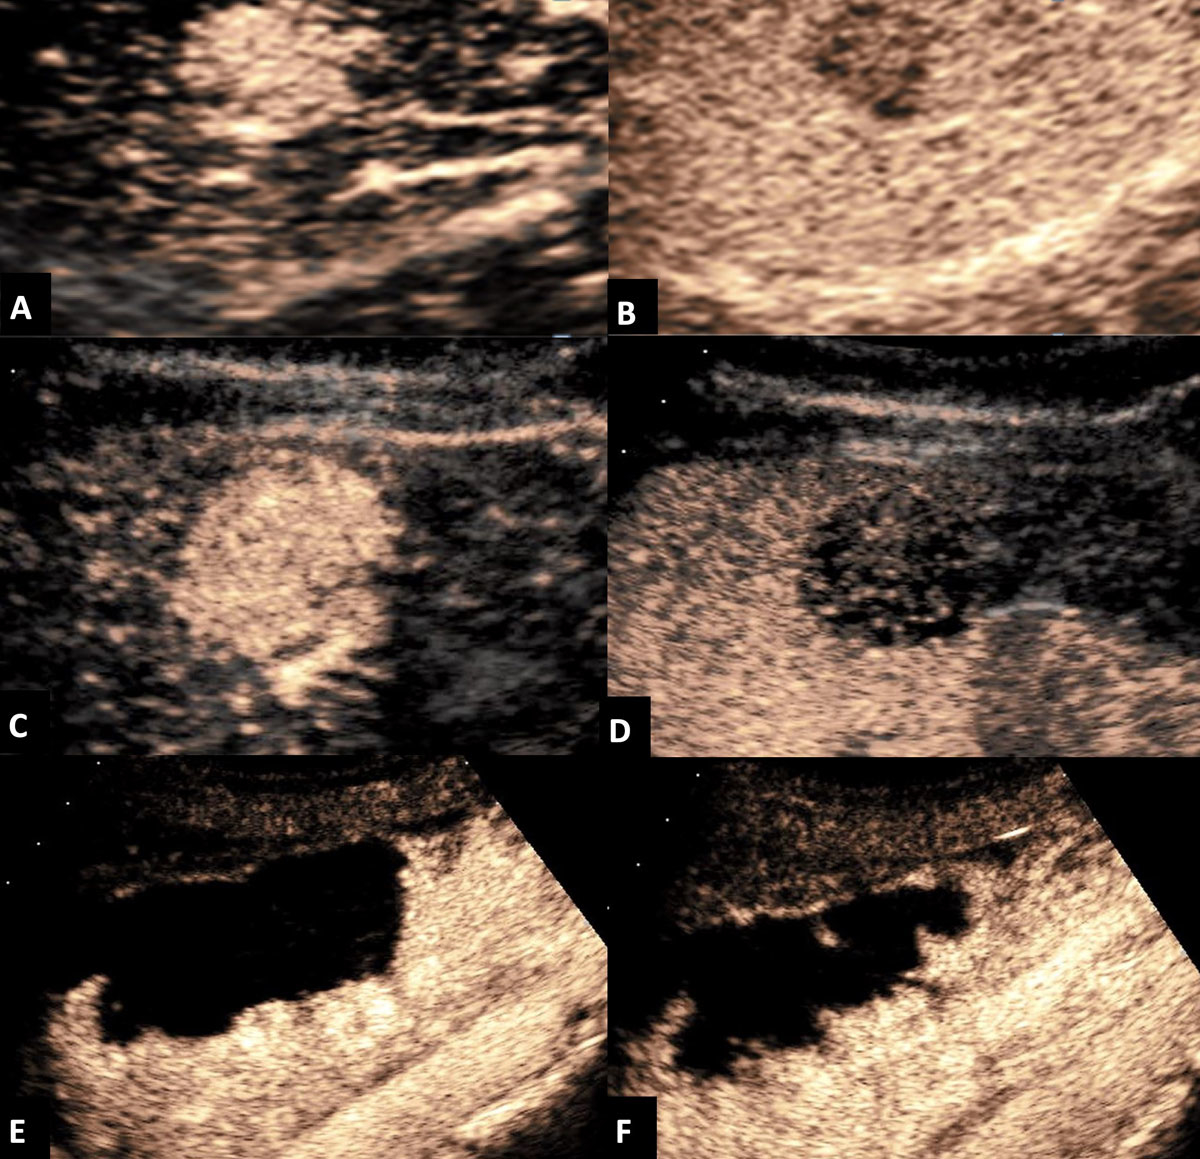

We retrospectively analysed all CEUSs of new or unclear FLLs performed at the Kantonsspital St. Gallen in Switzerland between November 2011 and March 2013. The anonymised data acquisition was approved by the ethics review committee of the canton of St Gallen (EKSG13/163). In all patients, the CEUS results (benign versus malignant FLLs) were compared with the corresponding CT or MRI findings. CEUS was performed by a single experienced gastroenterologist (level II or higher according to the EFSUMB [9]) using one ultrasound device (Acuson Sequoia 512®, Siemens, Erlangen, Germany) to avoid interobserver variation. A specific contrast agent (microbubbles, consisting of gas bubbles stabilised by a shell) was administered by an intravenous line. The vascular architecture of the lesion was evaluated in real time and with a higher temporal resolution than is possible with other imaging modalities, and was compared to the adjacent liver tissue. All patients were examined using the intravenous application of Sonovue® (Bracco SpA, Milan, Italy), which was introduced in 2001 and is licensed in Europe. It contains sulphur hexafluoride in a phospholipid shell. This can be performed in the same session using the same ultrasound device if it is equipped with specific software for CEUS. The 1.5 to 2.0 ml contrast agent dose was administered as a bolus injection into the antecubital vein using an intravenous line. The line was at least 20G to avoid microbubble destruction during injection. After injection of Sonovue®, the contrast enhancement of lesions was examined during the three vascular phases, i.e. during the arterial phase, the portal venous phase and the late venous phase (table 1) [8], using a timer. Intermittent scanning lasted up to five minutes. Arterial enhancement (“wash-in”) of the contrast agent in an FLL followed by hypoechoic appearance (“wash-out” = black hole in the liver parenchyma) in the portal venous or late venous phase was considered to indicate malignant FLL (fig. 1). We used a high mechanical index / power to destroy the microbubbles during the arterial phase to represent typical vascularisation of the lesion. An FLL with arterial enhancement without wash-out in any vascular phase was defined as a benign FLL [8, 10]. When the results were unclear, the Sonovue® injection was repeated a second or third time. Representative still images and video clips were recorded.

Figure 1 Contrast-enhanced ultrasound (CEUS) of (A) a cholangiocarcinoma showing early arterial enhancement and (B) wash-out in the venous phase. CEUS of a primary B-cell lymphoma demonstrating (C) early arterial enhancement at 15 seconds and (D) wash-out in the portal venous phase. CEUS of a haemangioma showing centripetal enhancement (E) at 21 seconds and (F) at 43 seconds.

In our analysis, false positive results using CEUS were in most cases due to atypical haemangiomas with arterioportal or arteriovenous shunts that had wash-out patterns which mimicked those of malignant FLLs. We believe that using the newest high-end ultrasound devices and appropriately experienced examiners will likely improve the rate of false positive results for haemangiomas. This is particularly likely when specific centripetal enhancement in the arterial and portal venous phases is demonstrated (see fig. 1).